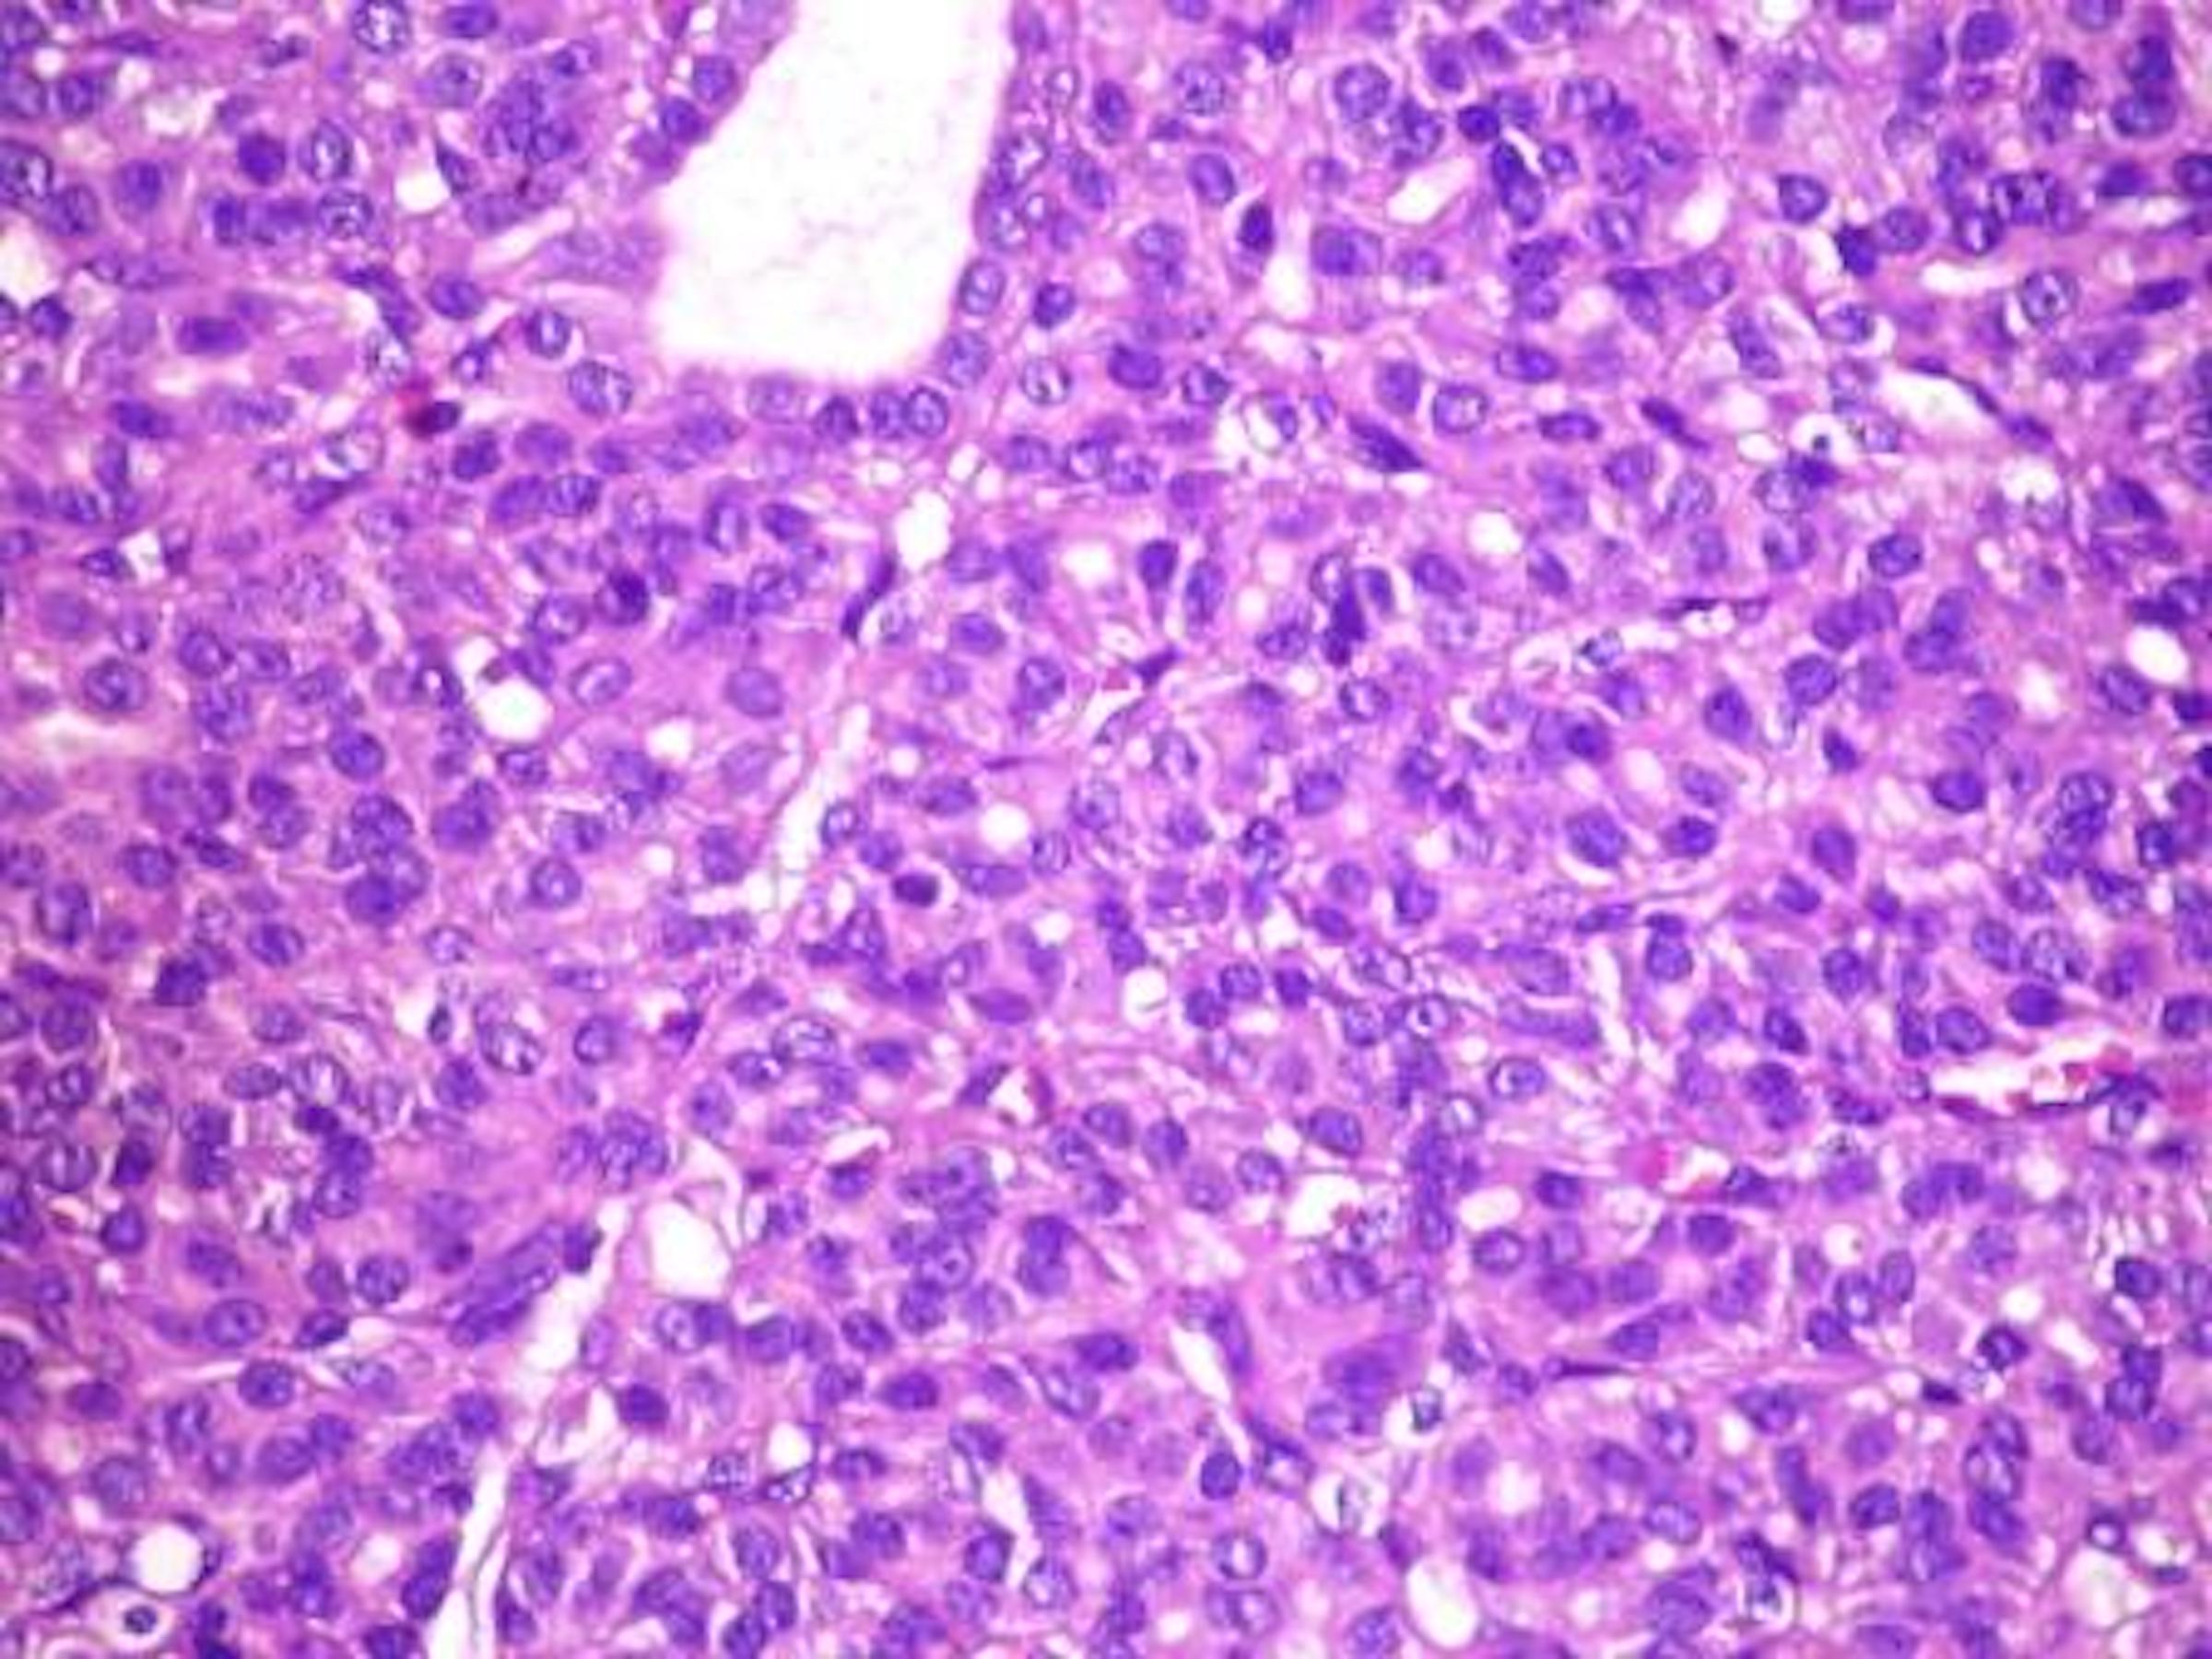

Microscopic (histologic) description

- Architectural patterns (can be seen in any combination)

- Microfollicular (fetal): smaller follicles, small amount of intraluminal colloid

- Solid / trabecular (embryonal): minimal or no colloid

- Cuboidal to low columnar cells

- Small round nuclei, smooth nuclear boundary, uniformly hyperchromatic or euchromatic, dense chromatin, absent nuclear features of papillary thyroid carcinoma, nuclear score 0 or 1 (JAMA Oncol 2016;2:1023)

- Inconspicuous nucleoli

- Mitoses are uncommon

- Scant stroma

- Variants

- Follicular adenoma with bizarre nuclei: may be seen after radiation exposure and in hyperfunctioning adenoma

Microscopic (histologic) images

Contributed by Shipra Agarwal, M.D., Andrey Bychkov, M.D., Ph.D., Mark R. Wick, M.D., Asmaa Gaber Abdou, M.D. and AFIP

Atypical adenomas: